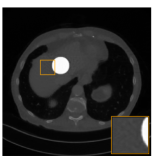

One particular advantage of aNETT over post-processing is the increased robustness with respect to the type of image to be reconstructed. To highlight this advantage, as illustrated in the top left image in Figure 3.3 we add a high intensity disc to the CT image shown in 3.1. The disc represents a clear low complexity structure and its accurate reconstruction should be easily possible.

Fig. 3.3: Reconstruction from data with additional structure.

Figure 3.3 shows the reconstructions using the FBP, the post-processing network and the aNETT. Taking a look at the zoomed in square in these images we see that FBP well reconstructs the circle. The post-processing network output, however, has some dark spots close to the circle and generally shows data-inconsistent behaviour around the circle. On the other hand, using the aNETT we see that these problems do not occur. This improved accuracy is because aNETT takes into account the given data even for images different form the training data.